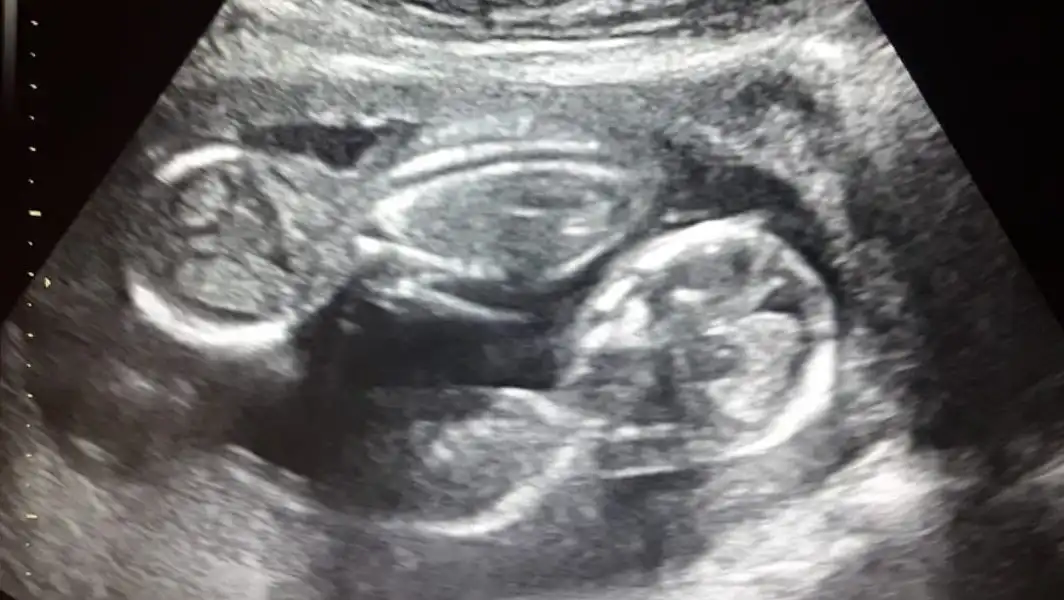

¿Qué se realiza en el ultrasonido de estos embarazos?

• ❤ Evaluación de la corionicidad, es decir si se trata de un embarazo gemelar con una placenta en la que ambos gemelos la comparten o bien dos placentas, una para cada gemelo, ya que de acuerdo a ello será la vigilancia en estos embarazos

• ❤ Si son embarazos gemelares con una sola placenta, la evaluación y el seguimiento deberá ser más estrecho, ya que que hay mayor riesgo de complicaciones en estos embarazos.

• ❤ La ecografía es el mejor método diagnóstico no sólo para identificar una gestación gemelar, sino también para catalogarla y especificar su corionicidad (número de placentas) y su amniocidad (número de bolsas).